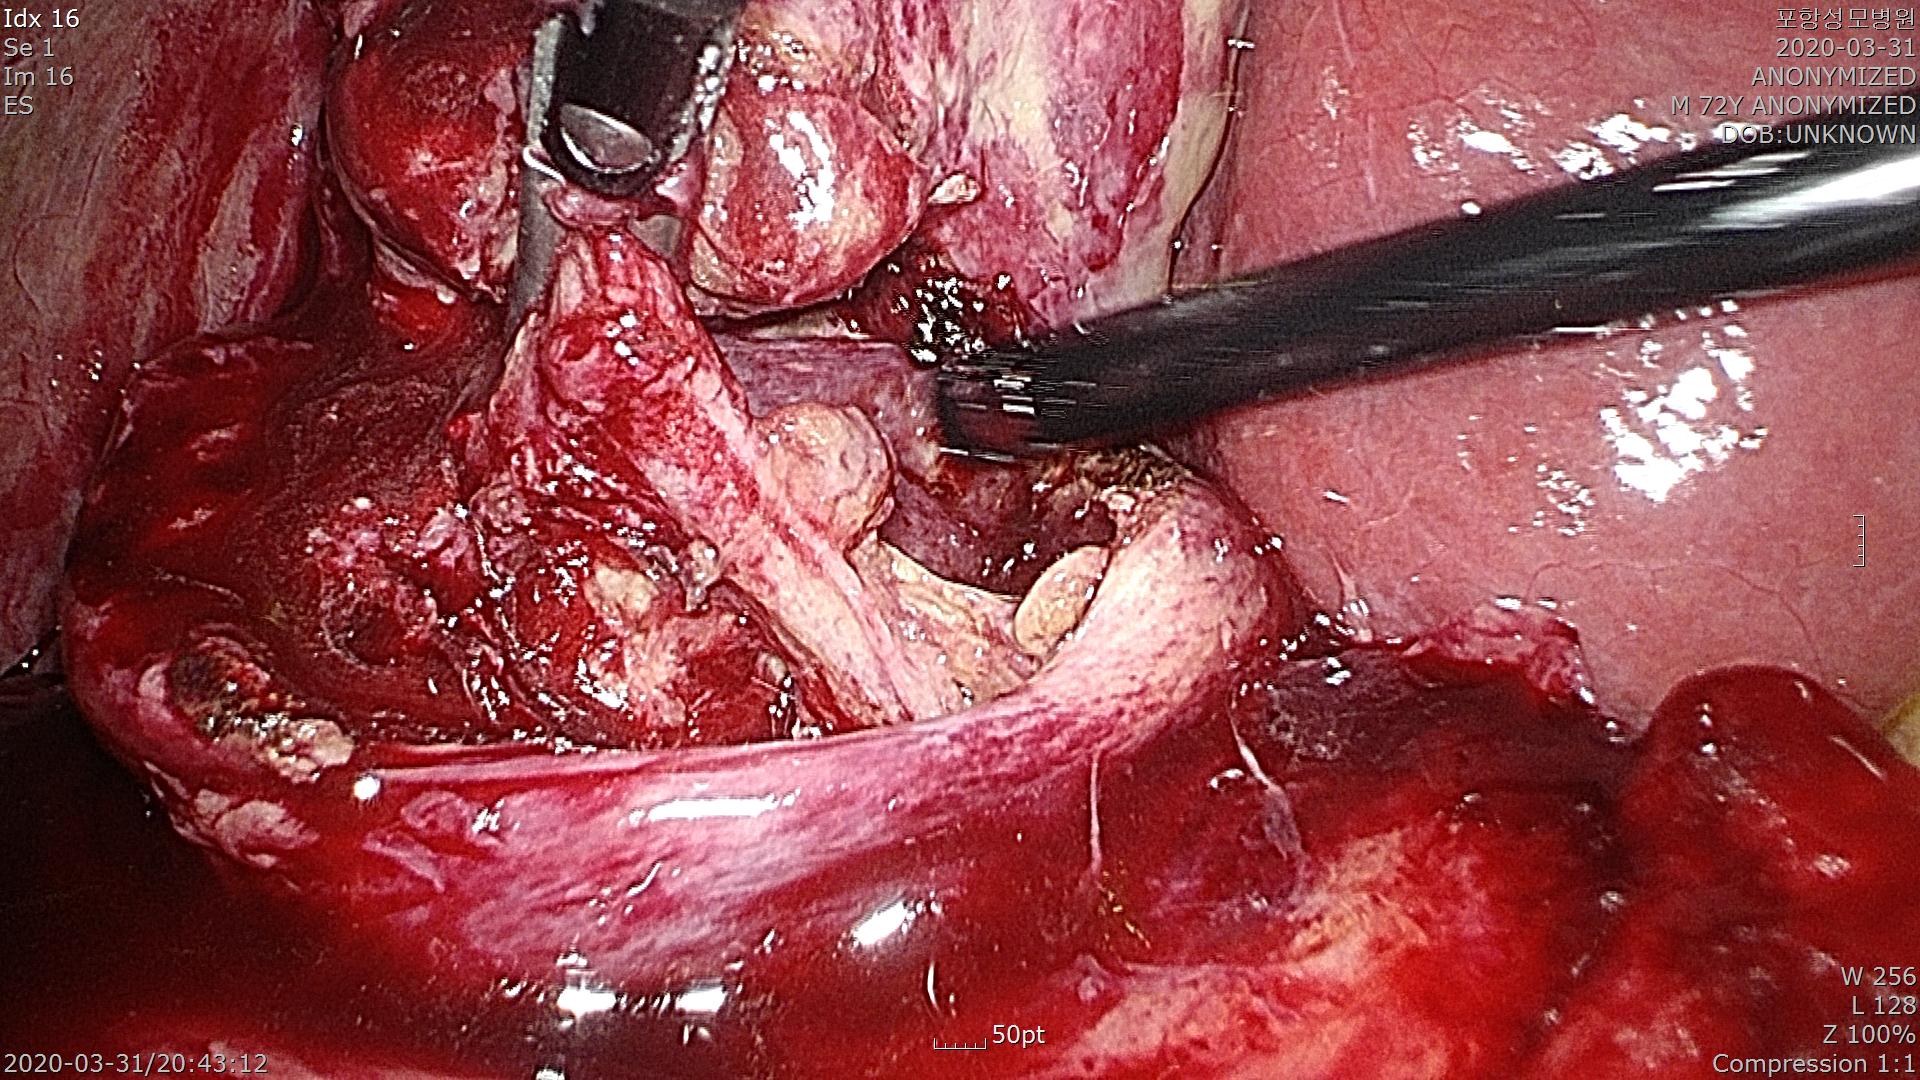

먼저 담낭을 먹여살리는 혈관을 노출시켜,

혈관클립으로 결찰한 후 혈관을 잘라냅니다.

총담관으로 들어가는 담낭관은 염증이 심합니다.

담낭관이 굵어 클립으로 담낭관을 묶기는 어렵습니다. 그래서 복강경 수술기구인 Endo-loop를 이용하여 담낭관을 결찰합니다.

혹시나 담낭관이 샐까 싶어 2번 결찰했습니다.